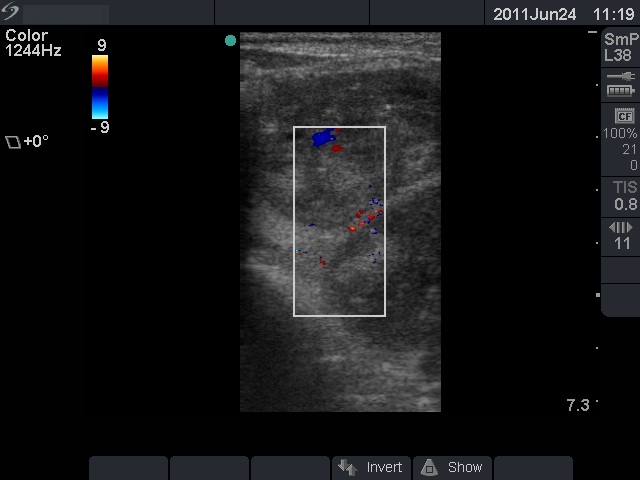

Anaplastic carcinoma - Case 10. |

Clinical data: a 75-year-old woman was referred for an evaluation of a progressive thyroid enlargement. The patient was operated on benign nodular goiter 50 years earlier. She told that her thyroid was enlarged just after the operation but caused no complaints. She noticed a sudden increase in the last two months, which caused dyspnea and dysphagia.

Palpation: a very hard, almost fixed left thyroid.

Ultrasonography: an extremely enlarged left thyroid which was composed of multiple hypoechogenic nodules. The dimensions of the left lobe were 150x180x350 mm.

Cytological report: anaplastic cancer.

Histopathology: anaplastic cancer.